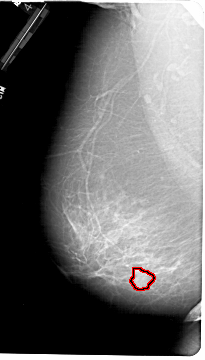

A_1190_1.RIGHT_MLO

RIGHT_MLO LINES 6706 PIXELS_PER_LINE 3601 BITS_PER_PIXEL 12 RESOLUTION 43.5 NON_OVERLAY

FILE: A_1190_1.LEFT_MLO.OVERLAY

TOTAL_ABNORMALITIES 1

ABNORMALITY 1

LESION_TYPE MASS SHAPE ROUND MARGINS ILL_DEFINED

ASSESSMENT 4

SUBTLETY 3

PATHOLOGY MALIGNANT

TOTAL_OUTLINES 1

BOUNDARY